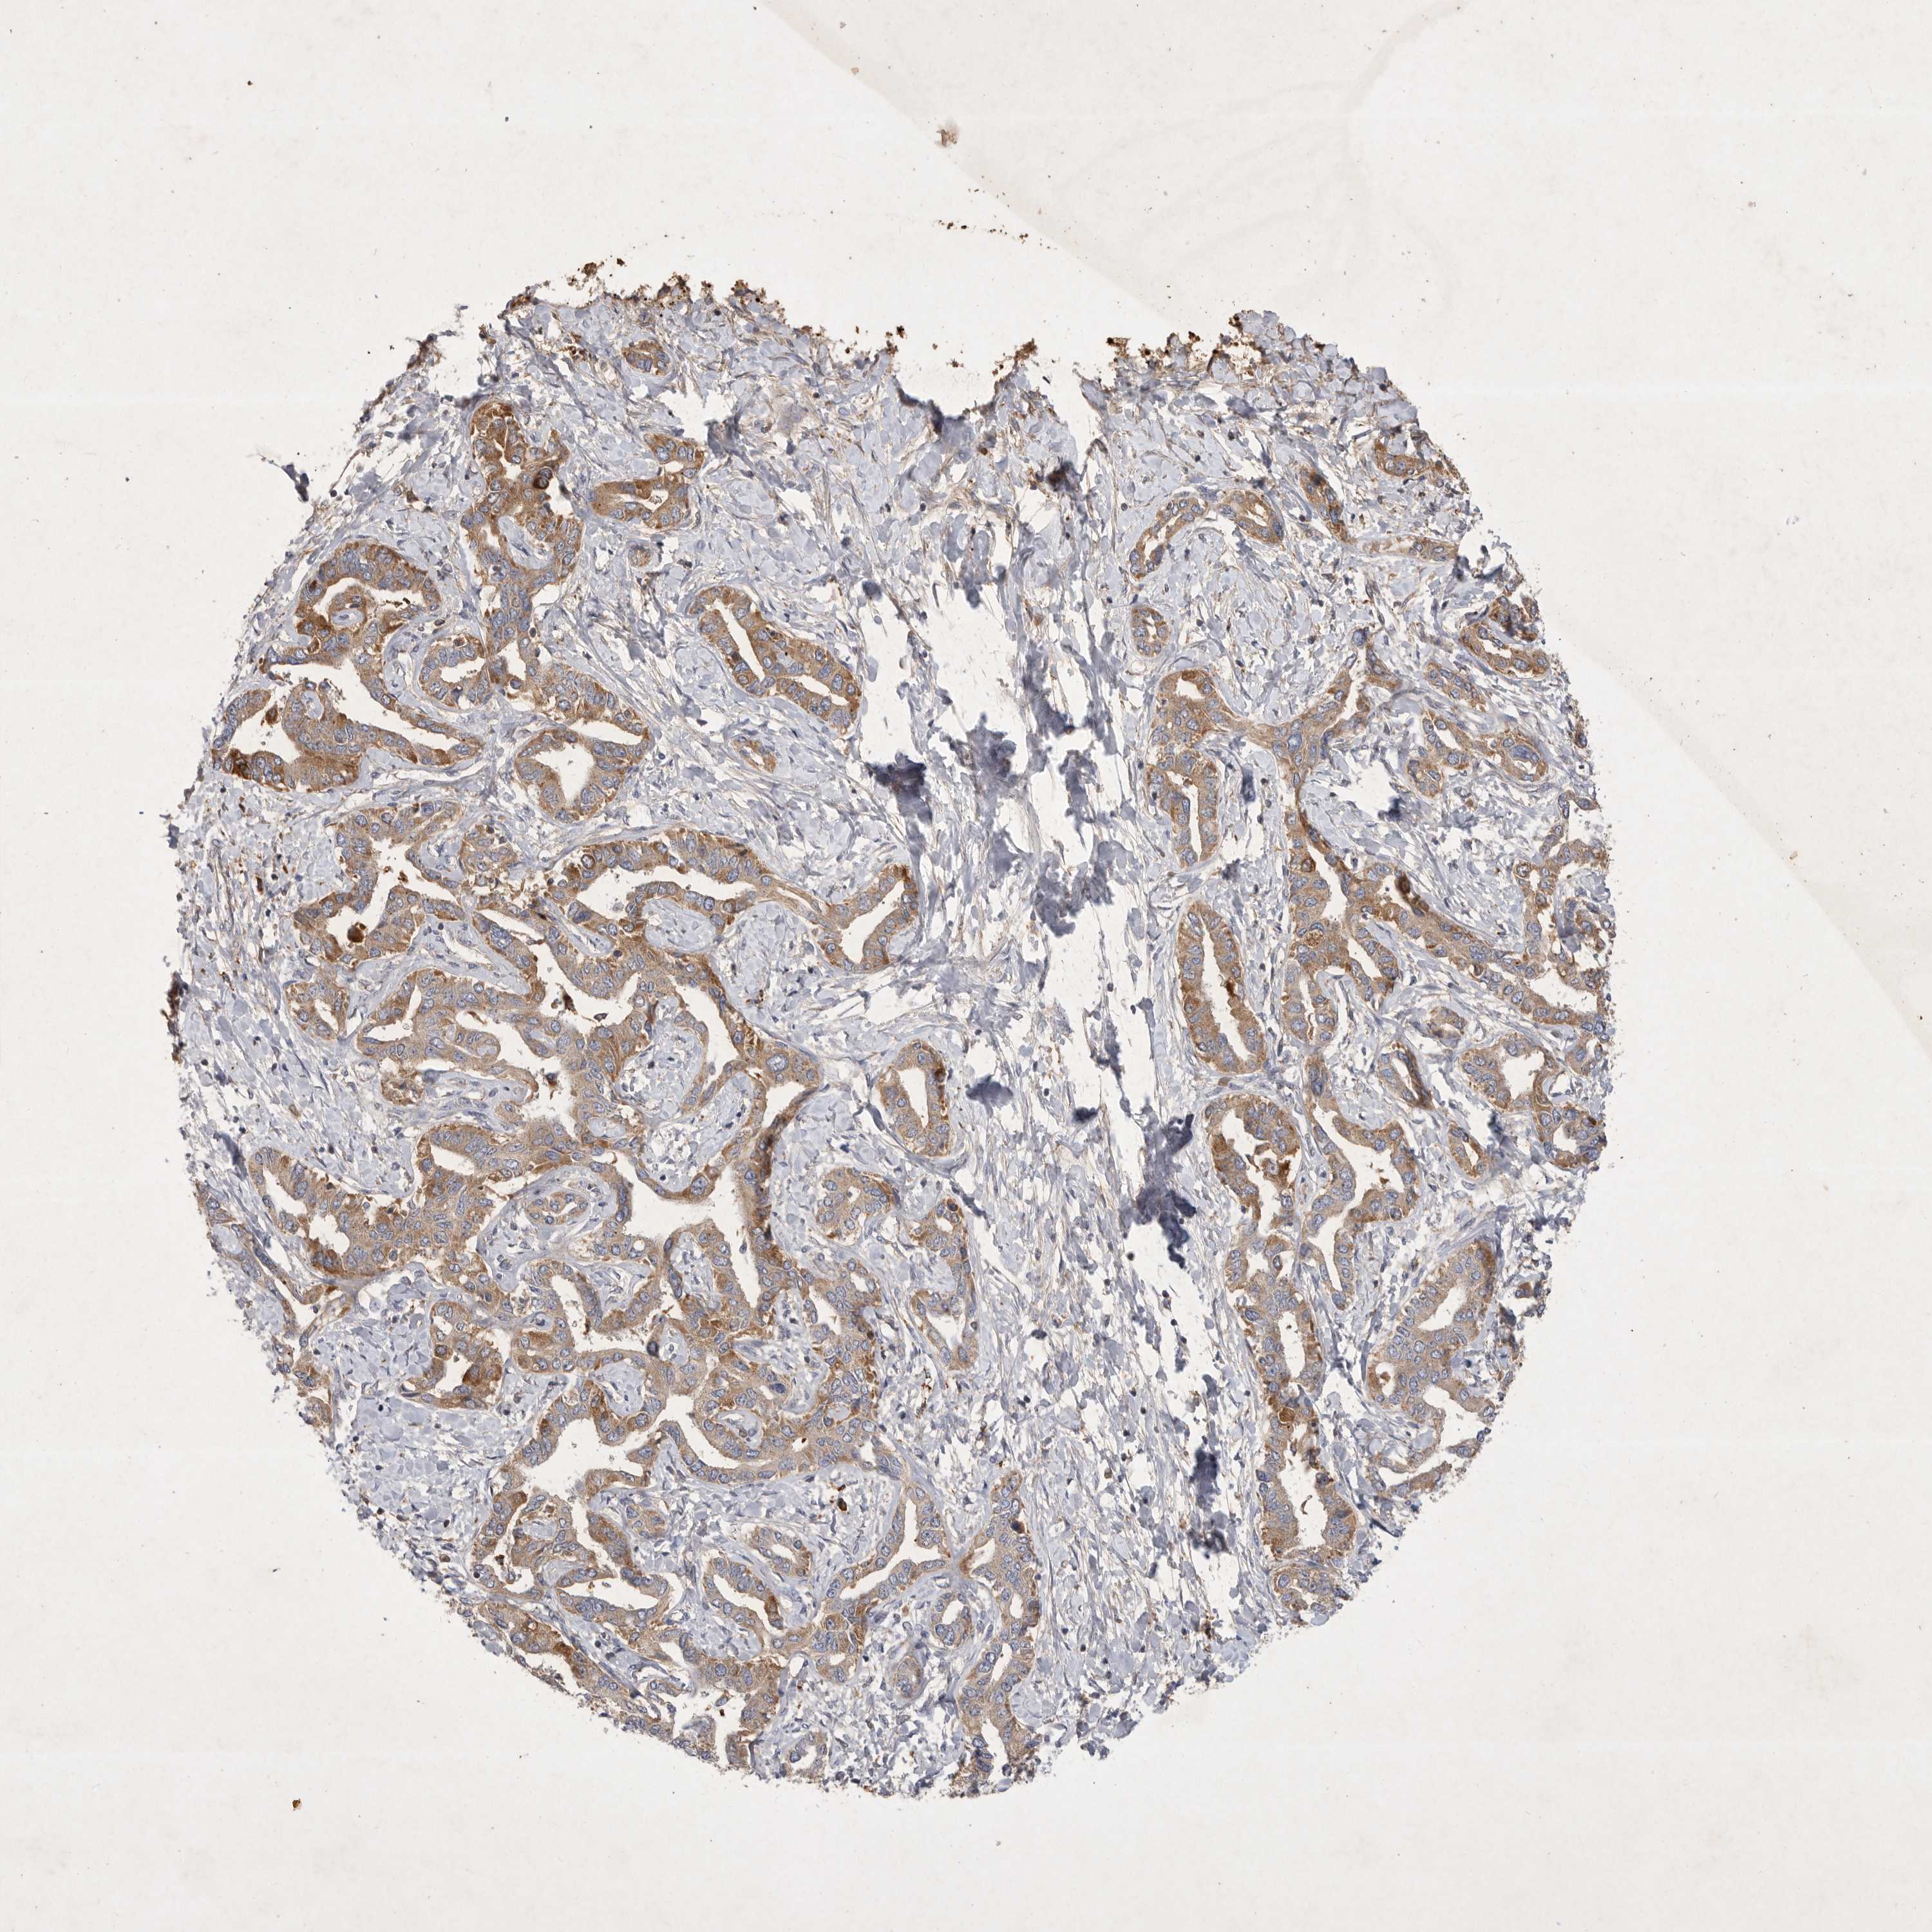

LIVER CANCER - Protein expressioni

A mouse-over function shows sample information and annotation data. Click on an image to view it in a full screen mode. Samples can be filtered based on level of antibody staining by selecting one or several of the following categories: high, medium, low and not detected. The assay and annotation is described here.

Note that samples used for immunohistochemistry by the Human Protein Atlas do not correspond to samples in the TCGA dataset.

Antibody stainingi

Antibody staining in the annotated cell types in the current human tissue is reported as not detected, low, medium, or high, based on conventional immunohistochemistry profiling in selected tissues. This score is based on the combination of the staining intensity and fraction of stained cells.

Each image is clickable and will lead to virtual microscopy that enables deeper exploration of all samples and also displays staining intensity scores, fraction scores and subcellular localization as well as patient and tissue information for each sample.

Antibody HPA024550

Antibody HPA027160

Staining

High

Medium

Low

Not detected

Intensity

Strong

Moderate

Weak

Negative

Quantity

>75%

75%-25%

<25%

None

Location

Nuclear

Cytoplasmic/membranous

Cytoplasmic/membranous,nuclear

Cholangiocarcinoma

Carcinoma, Hepatocellular, NOS